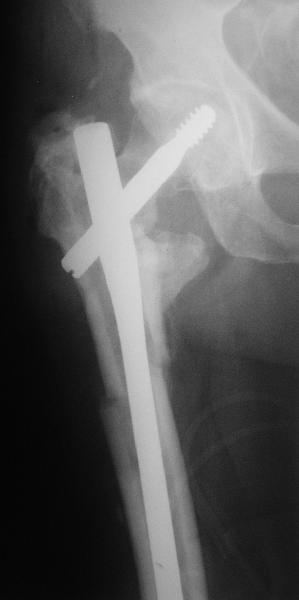

На прошлой неделе оперировали похожего пациента. 2 года после

неудачного остеосинтеза PFN в другом регионе. После удаления остатков

железа выявилось несращение вертельной области.

Поскольку в нашем случае выявилась подвижность, мы наложили дистрактор

таз-бедро на 3 дня, и сделали остеосинтез гаммой без остеотомии. То,

что произошла "корригирующая остеоклазия" в подвертельной области,

выявили после введения гвоздя. Пациент уже уехал домой, будем

наблюдать.